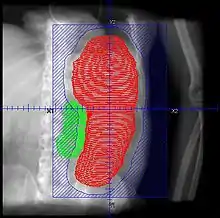

- No firm RT schedules, but low dose (<=1Gy) intermittent (2-3 fx/week), to total <=10 Gy recommended. One report suggests conventional 2 Gy/fx may be equally well tolerated. Consider dosing as follows (PMID 11230883 below):

- Lymphoproliferative: 4-10 Gy total in 1 Gy/fx

- Myelofibrosis: 1-9 Gy total, with 0.25-0.5 Gy/fx

- Patients should be continuously monitored, and fields adjusted with shrinking spleen

- RT should be stopped when therapeutic goal is achieved, rather than when prescription is reached

- Retrospective. 22 courses for 19 patients. Total dose 1.5 - 8.0 Gy (median 4.5 Gy), fractional dose 0.25 - 1 Gy delivered weekly or twice weekly. AP/PA. Median field reduction 25%

- Retrospective. 22 patients with 32 courses of SI. RT 0.25 - 0.5 Gy/fx, fields AP/PA and decreased with response, treatment halted with response